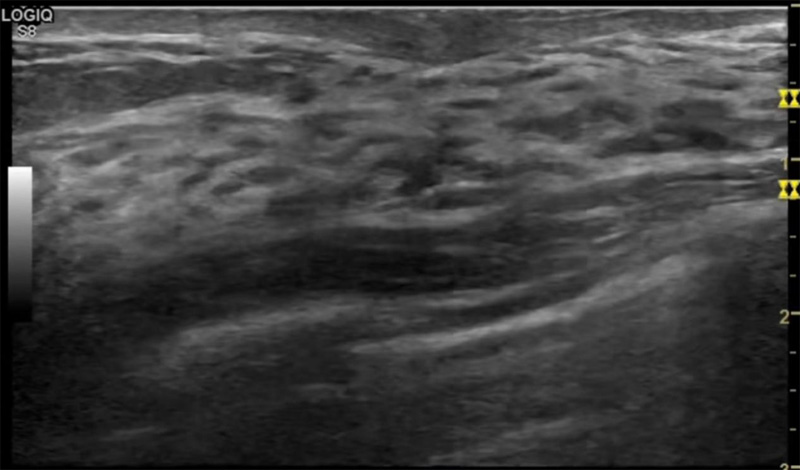

乳房脹痛,觸摸疼痛,手摸起來感覺有腫塊。這個(gè)是什么問題呢?醫(yī)生診斷一般是乳腺增生。那么在乳腺超聲設(shè)備檢查后,報(bào)告單卻顯示雙乳未見明顯占位性病變。乳腺增生是很多女性,特別是育齡期女性都有的經(jīng)歷、到底乳腺增生癥狀有哪些?會(huì)給我們帶來怎樣的影響呢?乳腺增生不是腫瘤跟炎癥。乳腺組織增生及退行性變跟內(nèi)分泌功能紊亂有關(guān)系。正常的生理改變。還有乳腺病,良性乳腺結(jié)構(gòu)不良等名稱。

乳腺增生有什么癥狀,病因?比較典型的就是乳房疼痛,特別是經(jīng)前癥狀比較重,經(jīng)后就有所緩解。有時(shí)候還能碰到乳房硬塊。根據(jù)經(jīng)期的變化而變化硬度大小都有變。乳腺在內(nèi)分泌激素,伴隨月經(jīng)周期有增生問題。內(nèi)分泌激素代謝失衡,雌激素水平增高,出現(xiàn)乳腺組織增生過度,增生組織不退的情況下,就會(huì)有乳腺增生癥狀。這個(gè)不會(huì)增加乳腺癌的風(fēng)險(xiǎn)。所以不用緊張的。不過乳腺癌的病人都會(huì)有乳腺增生。所以乳腺增長有沒癥狀,都需要進(jìn)行常規(guī)的體檢。